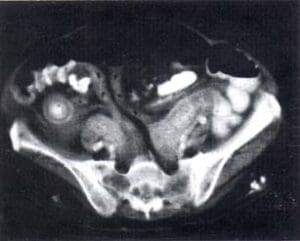

La TAC es el estudio de elección en la Trombosis Venosa Mesentérica (TVM) aguda, con una sensibilidad de 90%. (1, 13). Los hallazgos específicos consisten en engrosamiento e intensificación persistente de la pared intestinal, aumento de tamaño de la VMS con aumento de la densidad en su pared, lucidez central correspondiente a trombo luminal y vasos sanguíneos colaterales dilatados en un mesenterio engrosado (2) (figura 1).

FIGURA 1. TAC ABDOMINAL. TROMBO INTRALUMINAL EN LA VENA MESENTÉRICA

FIGURA 2. TAC ABDOMINAL. ENGROSAMIENTO DE LA PARED INTESTINAL